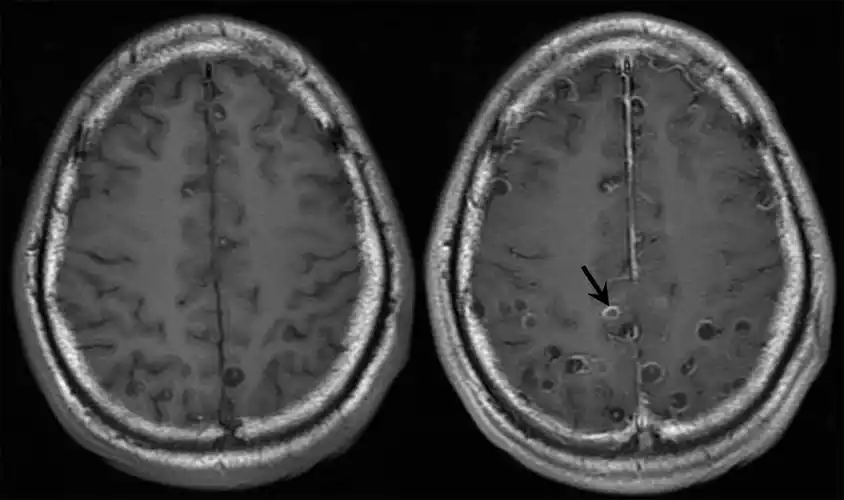

一文读懂脑囊虫病的影像学表现